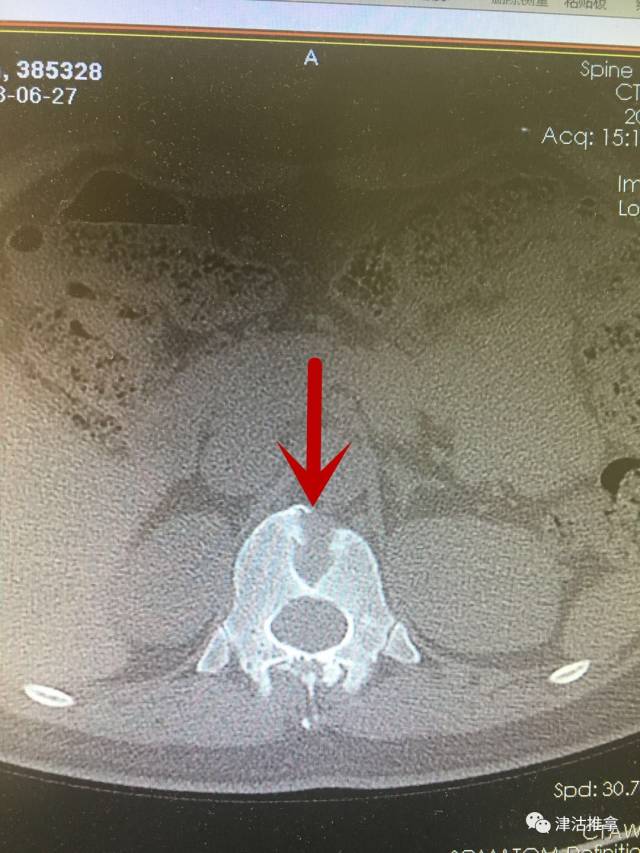

这是什么? 这个蝴蝶椎看着就很可怕,是一种骨折的形态?

图片尺寸640x853